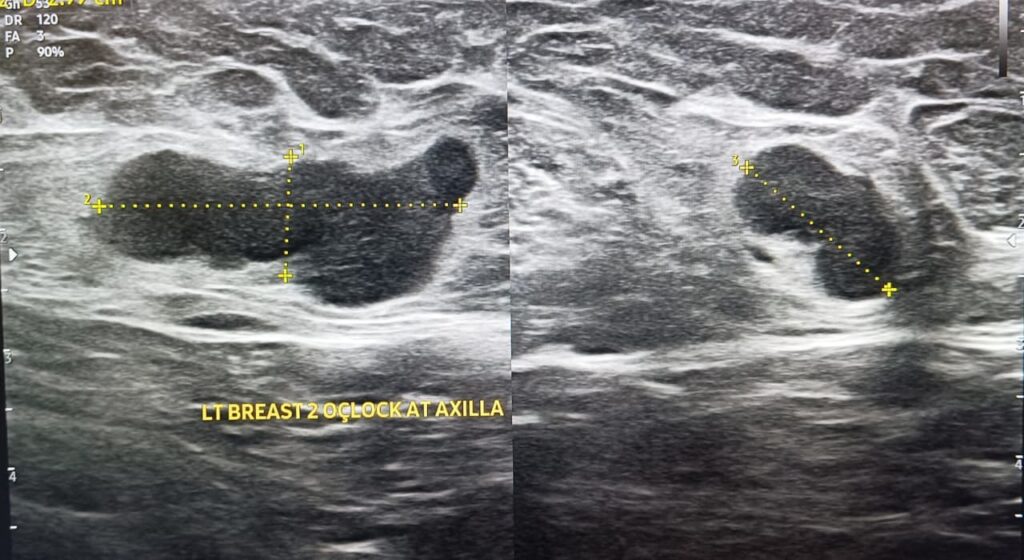

There was this 50-year-old lady, who presented to the physician with lump in left breast near axilla. There was no associated pain, but only a little discomfort. Apart from this ailment she was in a good health.

The lesion that the patient was referring to, was a harmless lump of breast, also known as a breast mouse. Another less than one centimetre sized similar focus was noted in the medial upper quadrant.

These were benign lesions. They only required follow ups over a period of time.